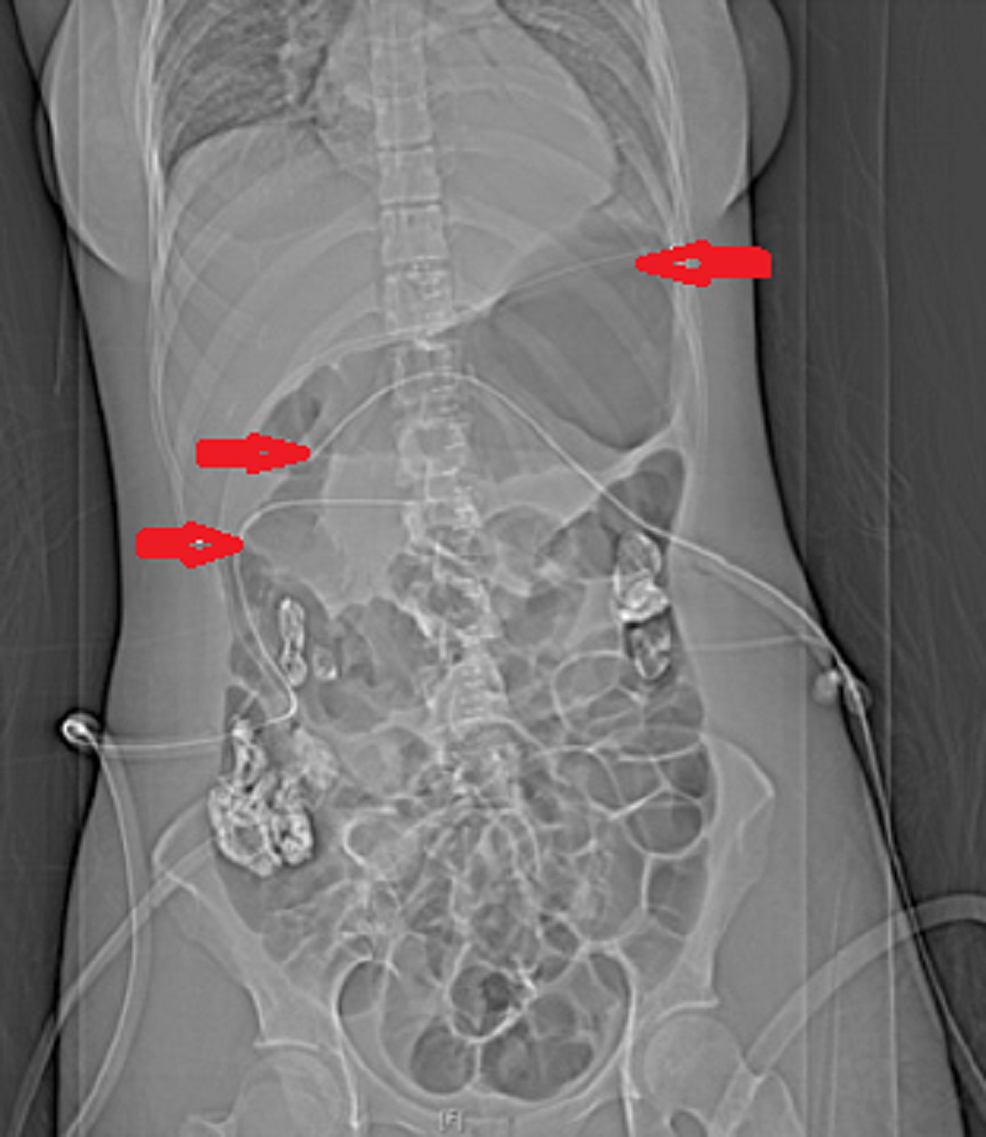

Cureus Therapeutic Serendipity Secondary to Abdominal Drain in How To Empty An Abdominal Drain To empty, lift the pop top on the collection bulb, and squeeze the fluid into a measuring cup with incremental markings (fl oz or cc). Follow the specific instructions from your doctor (since they can vary). Emptying your drain 2 times a. Moffitt cancer center medical professionals present this video, which offers comprehensive instructions on how to manage. This drains. How To Empty An Abdominal Drain.